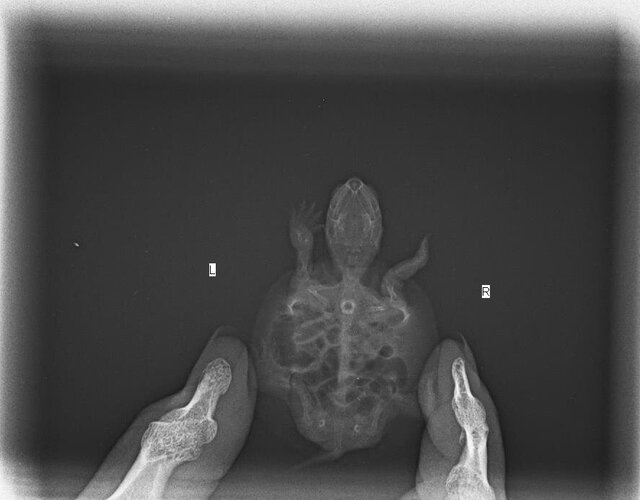

Добавляю рентген

по такой проекции не определяют пневмонию, на ней видно только жкт, лёгкие не видно, поэтому здесь стоит вопрос о квалификации врача.

@Mikki по снимку весь жкт был раздут, саму траву видно не будет, но если черепаха её ела - да, могла произойти закупорка и это тоже будет выглядеть как нарушение моторики на снимке.